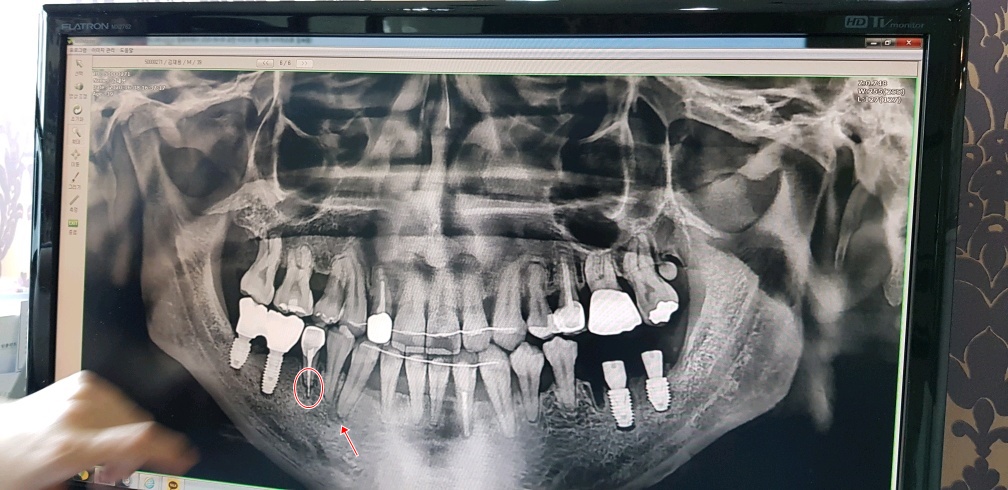

여기 원장님 말로는 엑스레이 보여주면서

다른 교정치과에서 치료했던 치아가 문제인것 같다 한다..

신경치료 하면서 심어놨던 하얀색(치아뿌리의 중간부분)이 치아뿌리 안쪽에만 있어야 되는데

뿌리를 넘어서서 아픈것일 수도 있다고 하고(실제로 살짝 딱딱한걸 깨물어 보면 통증이 장난아니다..)

두번째로는 화살표 표시해둔 부분 이부분이 치아뿌리 끝 부터 염증이 생겨서 아픈것 일수도 있다고 한다..

우선 임플란트수술 하고 집에 오긴 했으나 수술한 곳은 안아픈데 동그란표시해 둔 저 치아가 너무 아파서

몇시간 마다 진통제 없이는 못버틸 정도로 아프다...